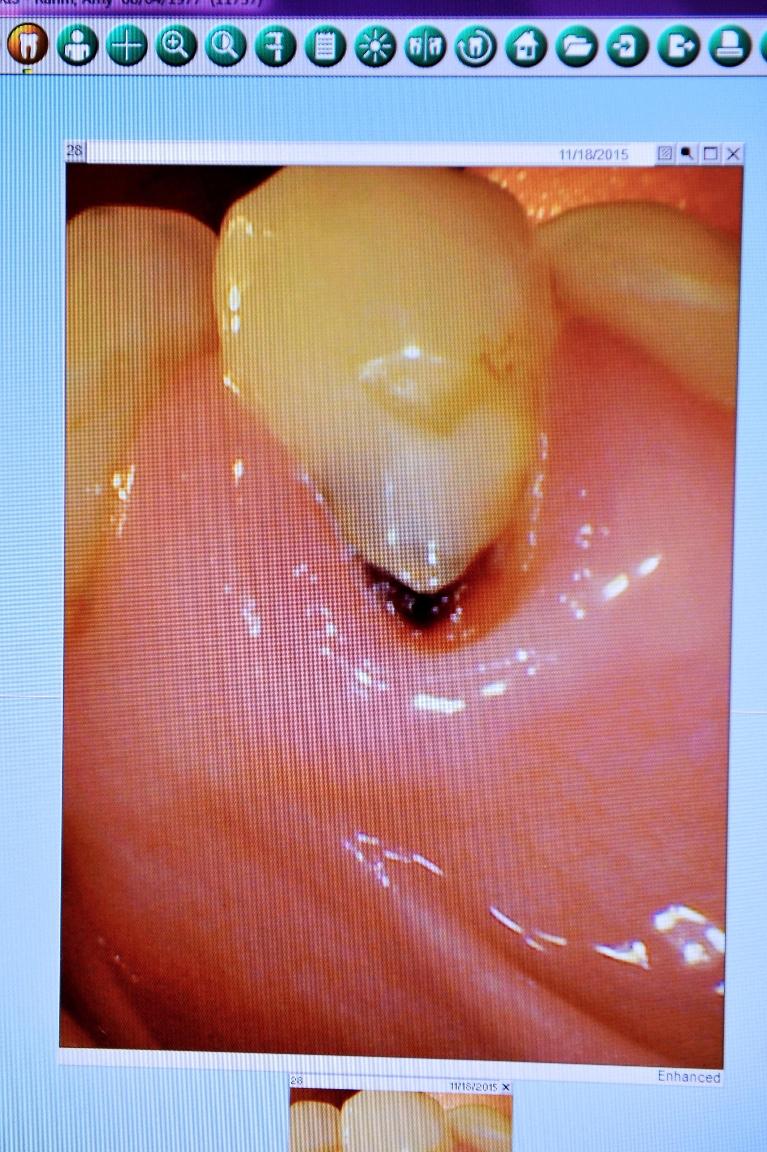

Intraoral Cameras

We use intraoral cameras to get a clear picture of your teeth and gums. The full-color video images of the inside of your mouth are enlarged and sent to a screen that you can comfortably view from the dental chair. We can point out problem areas and make recommendations for treatment.